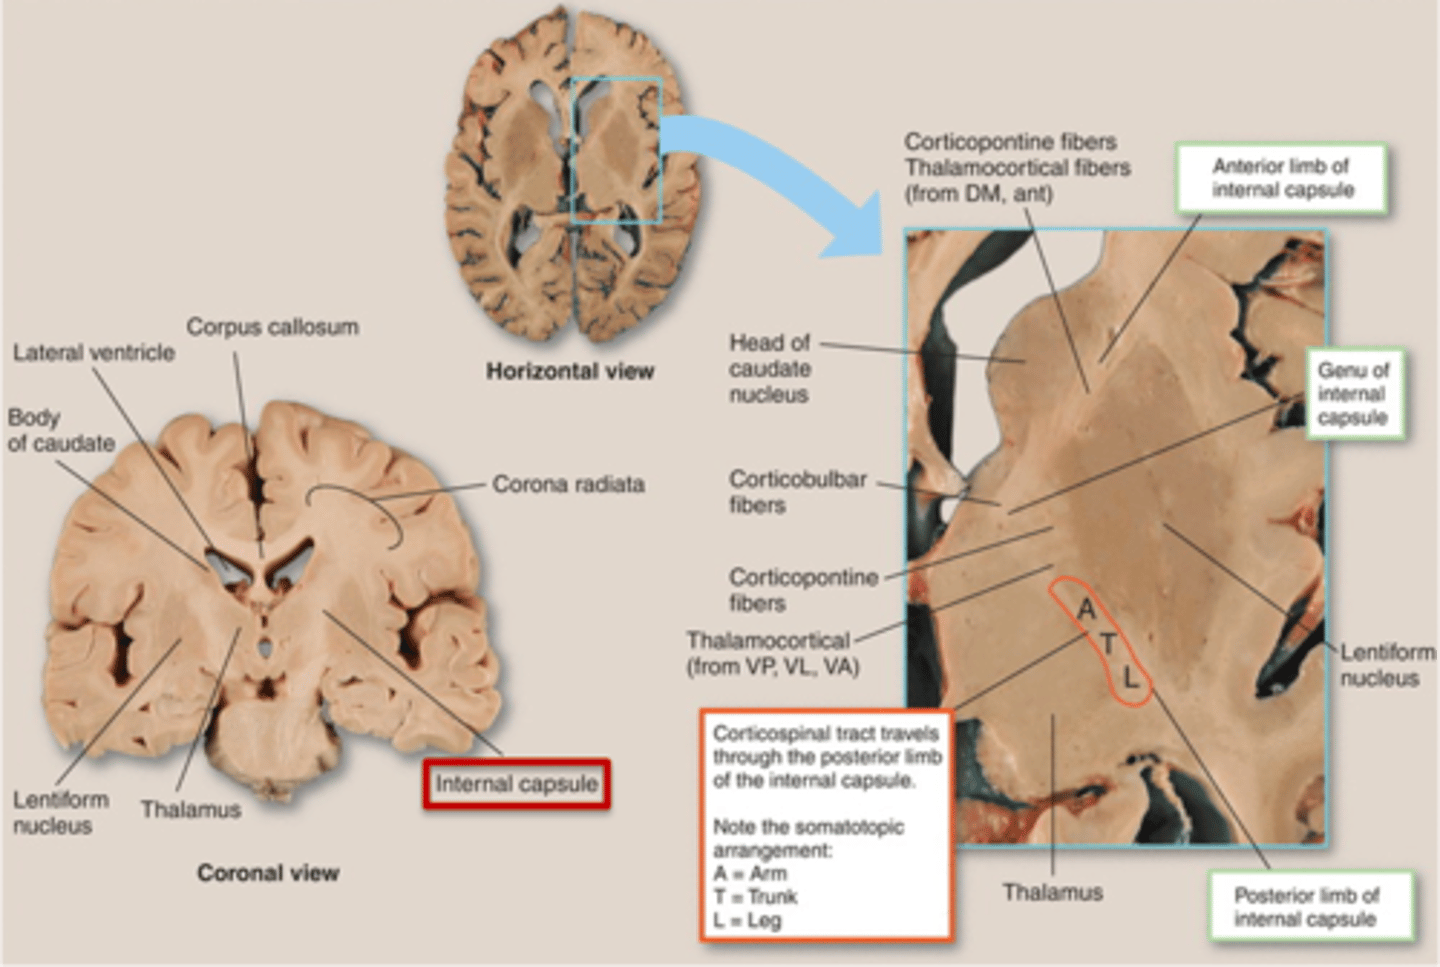

what are 3 key white matter structures found in the cerebrum?

1. corpus callosum

2. corona radiata

3. internal capsule

what cerebral white matter structure is a large bundle of nerve fibers that connects the left and right cerebral hemispheres, allowing them to communicate?

corpus callosum

what is the fan-shaped cerebral white matter sheet that is continuous ventrally with the internal capsule?

corona radiata

what cerebral white matter structure is a tract that carries sensory and motor information to and from the cerebral cortex?

internal capsule

what cerebral white matter structure is found between the basal ganglia?

internal capsule

what are the 3 regions of the internal capsule?

1. anterior limb

2. genu

3. posterior limb

what are the 3 parts of the basal ganglia? what runs between them?

1. caudate nucleus

2. putamen

3. globus pallidus

internal capsule

what part of the basal ganglia is the C-shaped structure that is most medial?

caudate nucleus

what part of the basal ganglia is medial to the putamen?

globus pallidus

the putamen and globus pallidus of the basal ganglia are collectively called the _______________ nucleus

lentiform